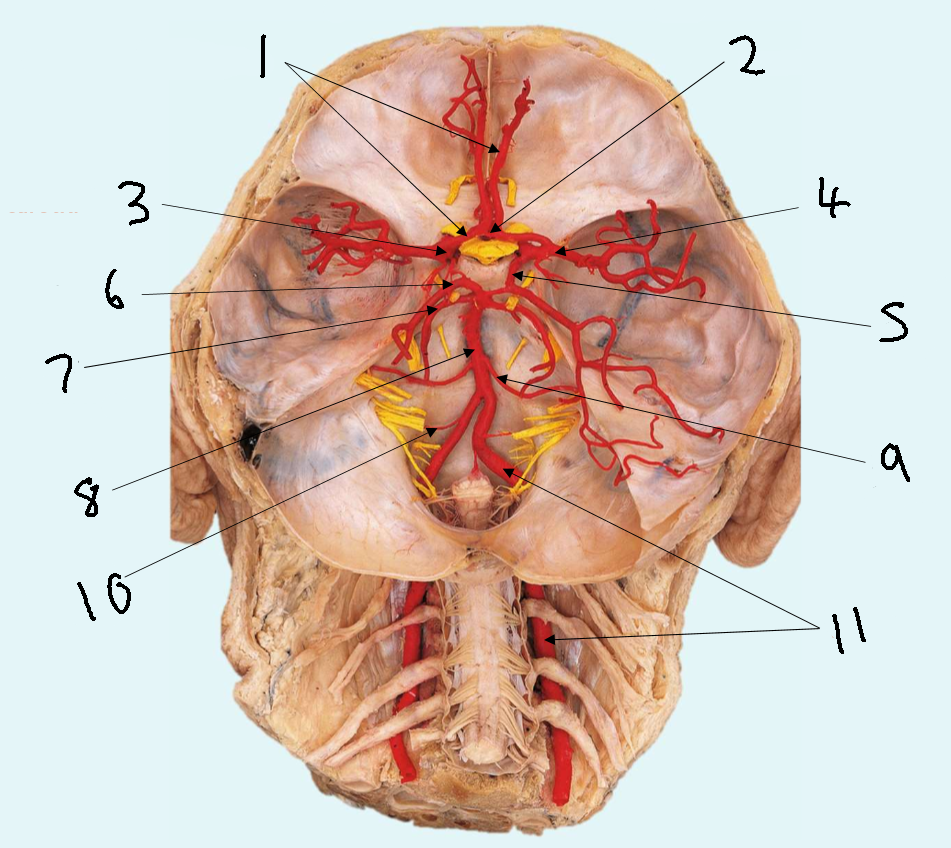

What is 1?

anterior cerebral artery

What is 2?

anterior communicating artery

What is 3?

internal carotid artery

What is 4?

posterior communicating artery

What is 5?

posterior cerebral artery

What is 6?

basilar artery

What is 7?

vertebral artery